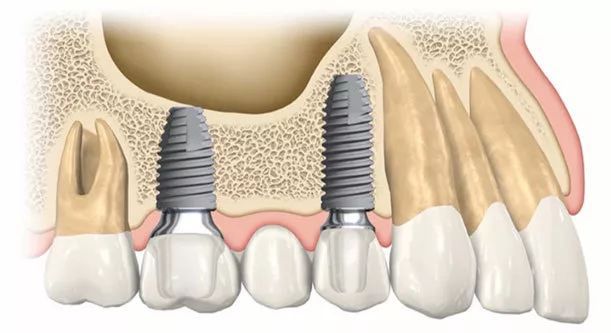

香港人去深圳種植牙是一個常見的選擇,因為深圳的牙科醫療水準和設備都非常先進,而且價格相對香港來說比較實惠。但是,香港人去深圳種植牙也需要注意一些事項:

瞭解手術的流程和風險

在進行種植牙手術前,香港人需要瞭解手術的流程和風險。可以通過和醫生溝通、查閱相關資料或者向其他有經驗的人尋求建議來瞭解手術的流程和注意事項。此外,香港人還需要瞭解手術的風險,如出血、感染、神經損傷等,並在手術前與醫生進行詳細的討論。